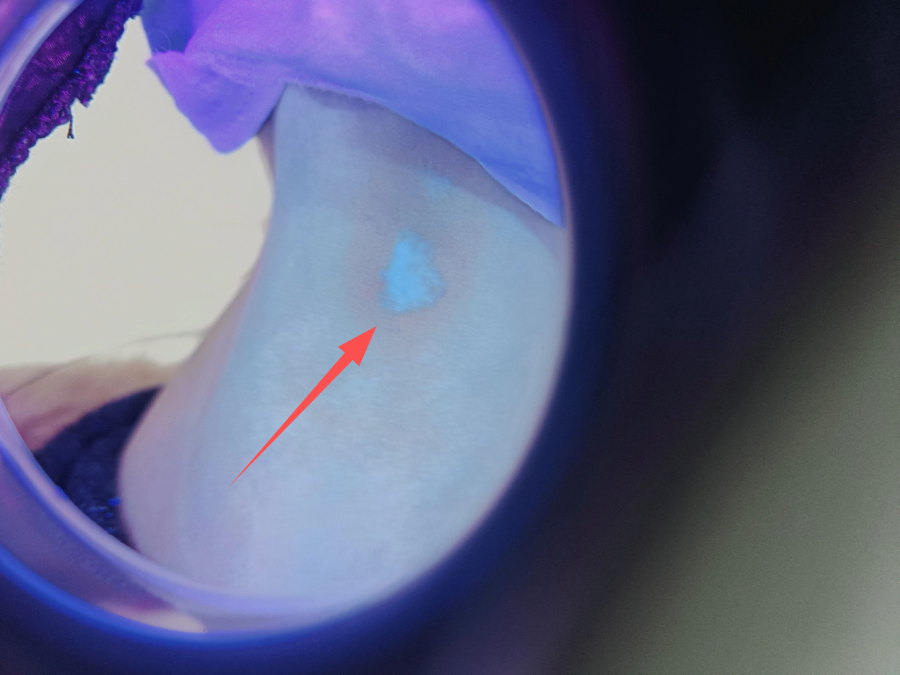

治疗前

治疗中 治疗后